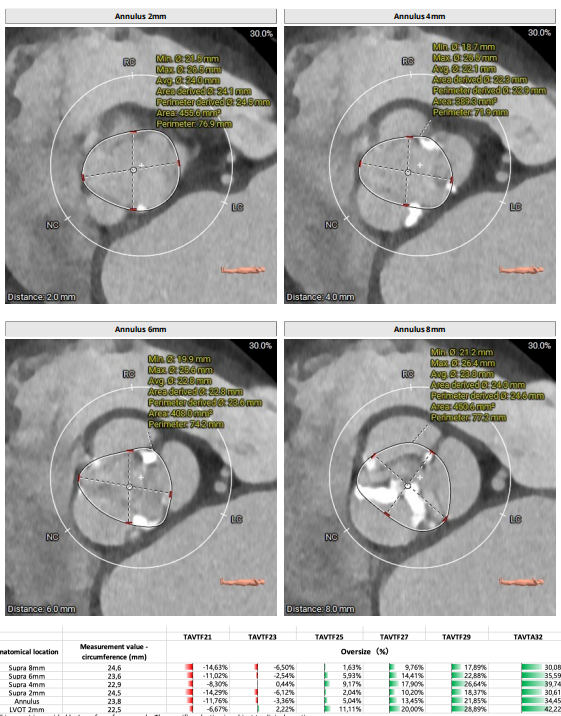

CASE1.

【术前CT】